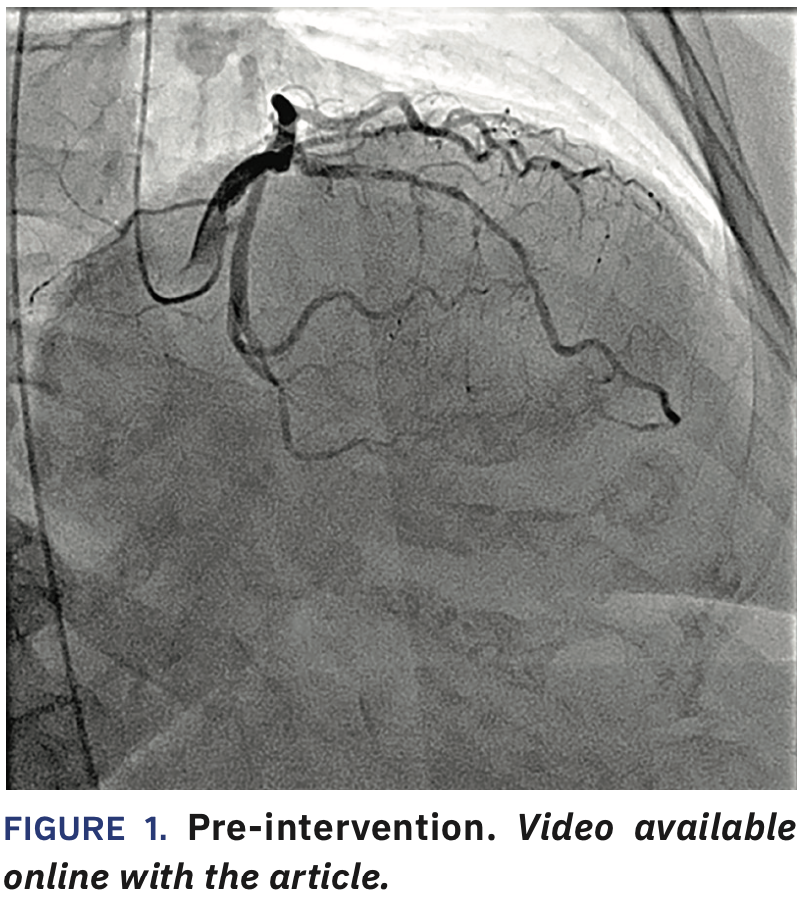

She was taken to the cardiac catheterization laboratory. Due to the small size of the patient’s radial arteries, 4 French (Fr) groin access was obtained via ultrasound with 4 Fr diagnostic catheters (Judkins Left [JL] 4, Judkins Right [R] 4) utilized to perform the diagnostic procedure (Figure 1, Video 1).

The JR4 was used to get left ventricular end diastolic pressure. The sheath was upsized to a 6 Fr size for the intervention and after giving heparin and 500 mcg nicardipine, a JL4 guide and Sion blue wire (Asahi Intecc) were used to cross the lesion. A 2.0 x 20 mm Apex balloon (Boston Scientific) was used to predilate the proximal to mid left anterior descending (LAD) coronary artery (up to 14-18 atmospheres [atm] for 7 seconds x3). 2.50 x 38 mm Synergy XD and 3.00 x 20 mm Synergy XD stents were placed (14 atm x1 and 14 atm x1), respectively in the mid and proximal vessel, followed by 2.50 x 20 mm (20 atm for 5 seconds x3) and 3.50 x 20 mm NC Apex (16 atm for 9 seconds x1) balloons. This was followed by an intravascular ultrasound (IVUS) run (Figures 2-3), resulting in further balloon dilatation with 2.75 x 15 mm (up to 16-25 atm for 7-11 seconds x4) and 3.75 x 15 mm Euphora NC (up to 18-25 atm for 7-8 seconds) (Medtronic) balloons in order to further dilate the under-expanded sections. We used CLEARstent Live (Siemens Healthineers) to help position the NC balloons. Final angiography showed a good result (Figure 4). The patient underwent closure with an Angio-Seal (Terumo) and she was placed on aspirin and ticagrelor, given the extent of stenting.